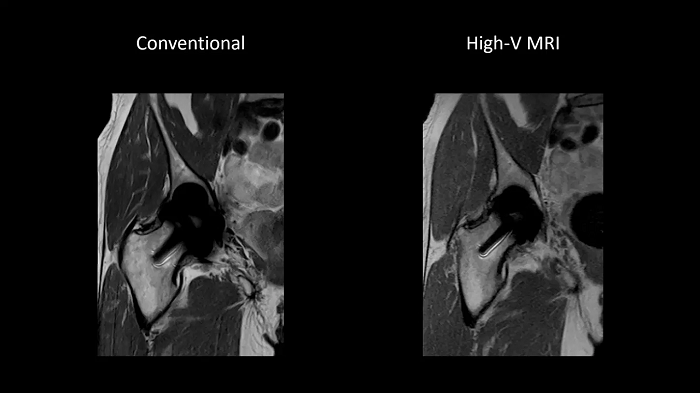

Improved implant imaging with High-V MRI

The imaging of metal implants has historically been difficult with conventional MRI systems as metal causes artifacts. High-V MRI offers intrinsic physical advantages that result in reduced metal distortions and strongly improved diagnostic capabilities for implant imaging.

80 cm bore MAGNETOM Free.Max

Image Courtesy: University Hospital Erlangen, Germany | Image-ID: 1aaaa3623 | 4aaaa0399